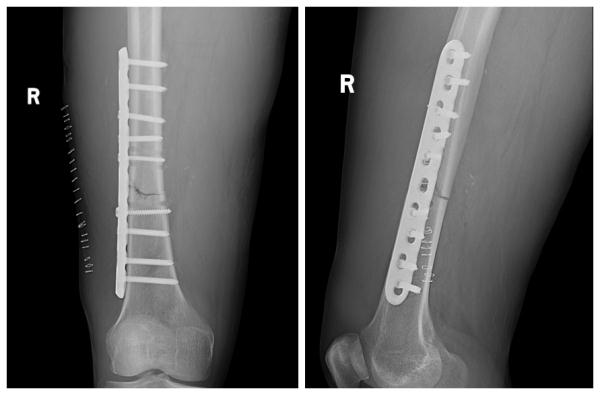

股骨干骨折钢板固定

图片尺寸2736x2736